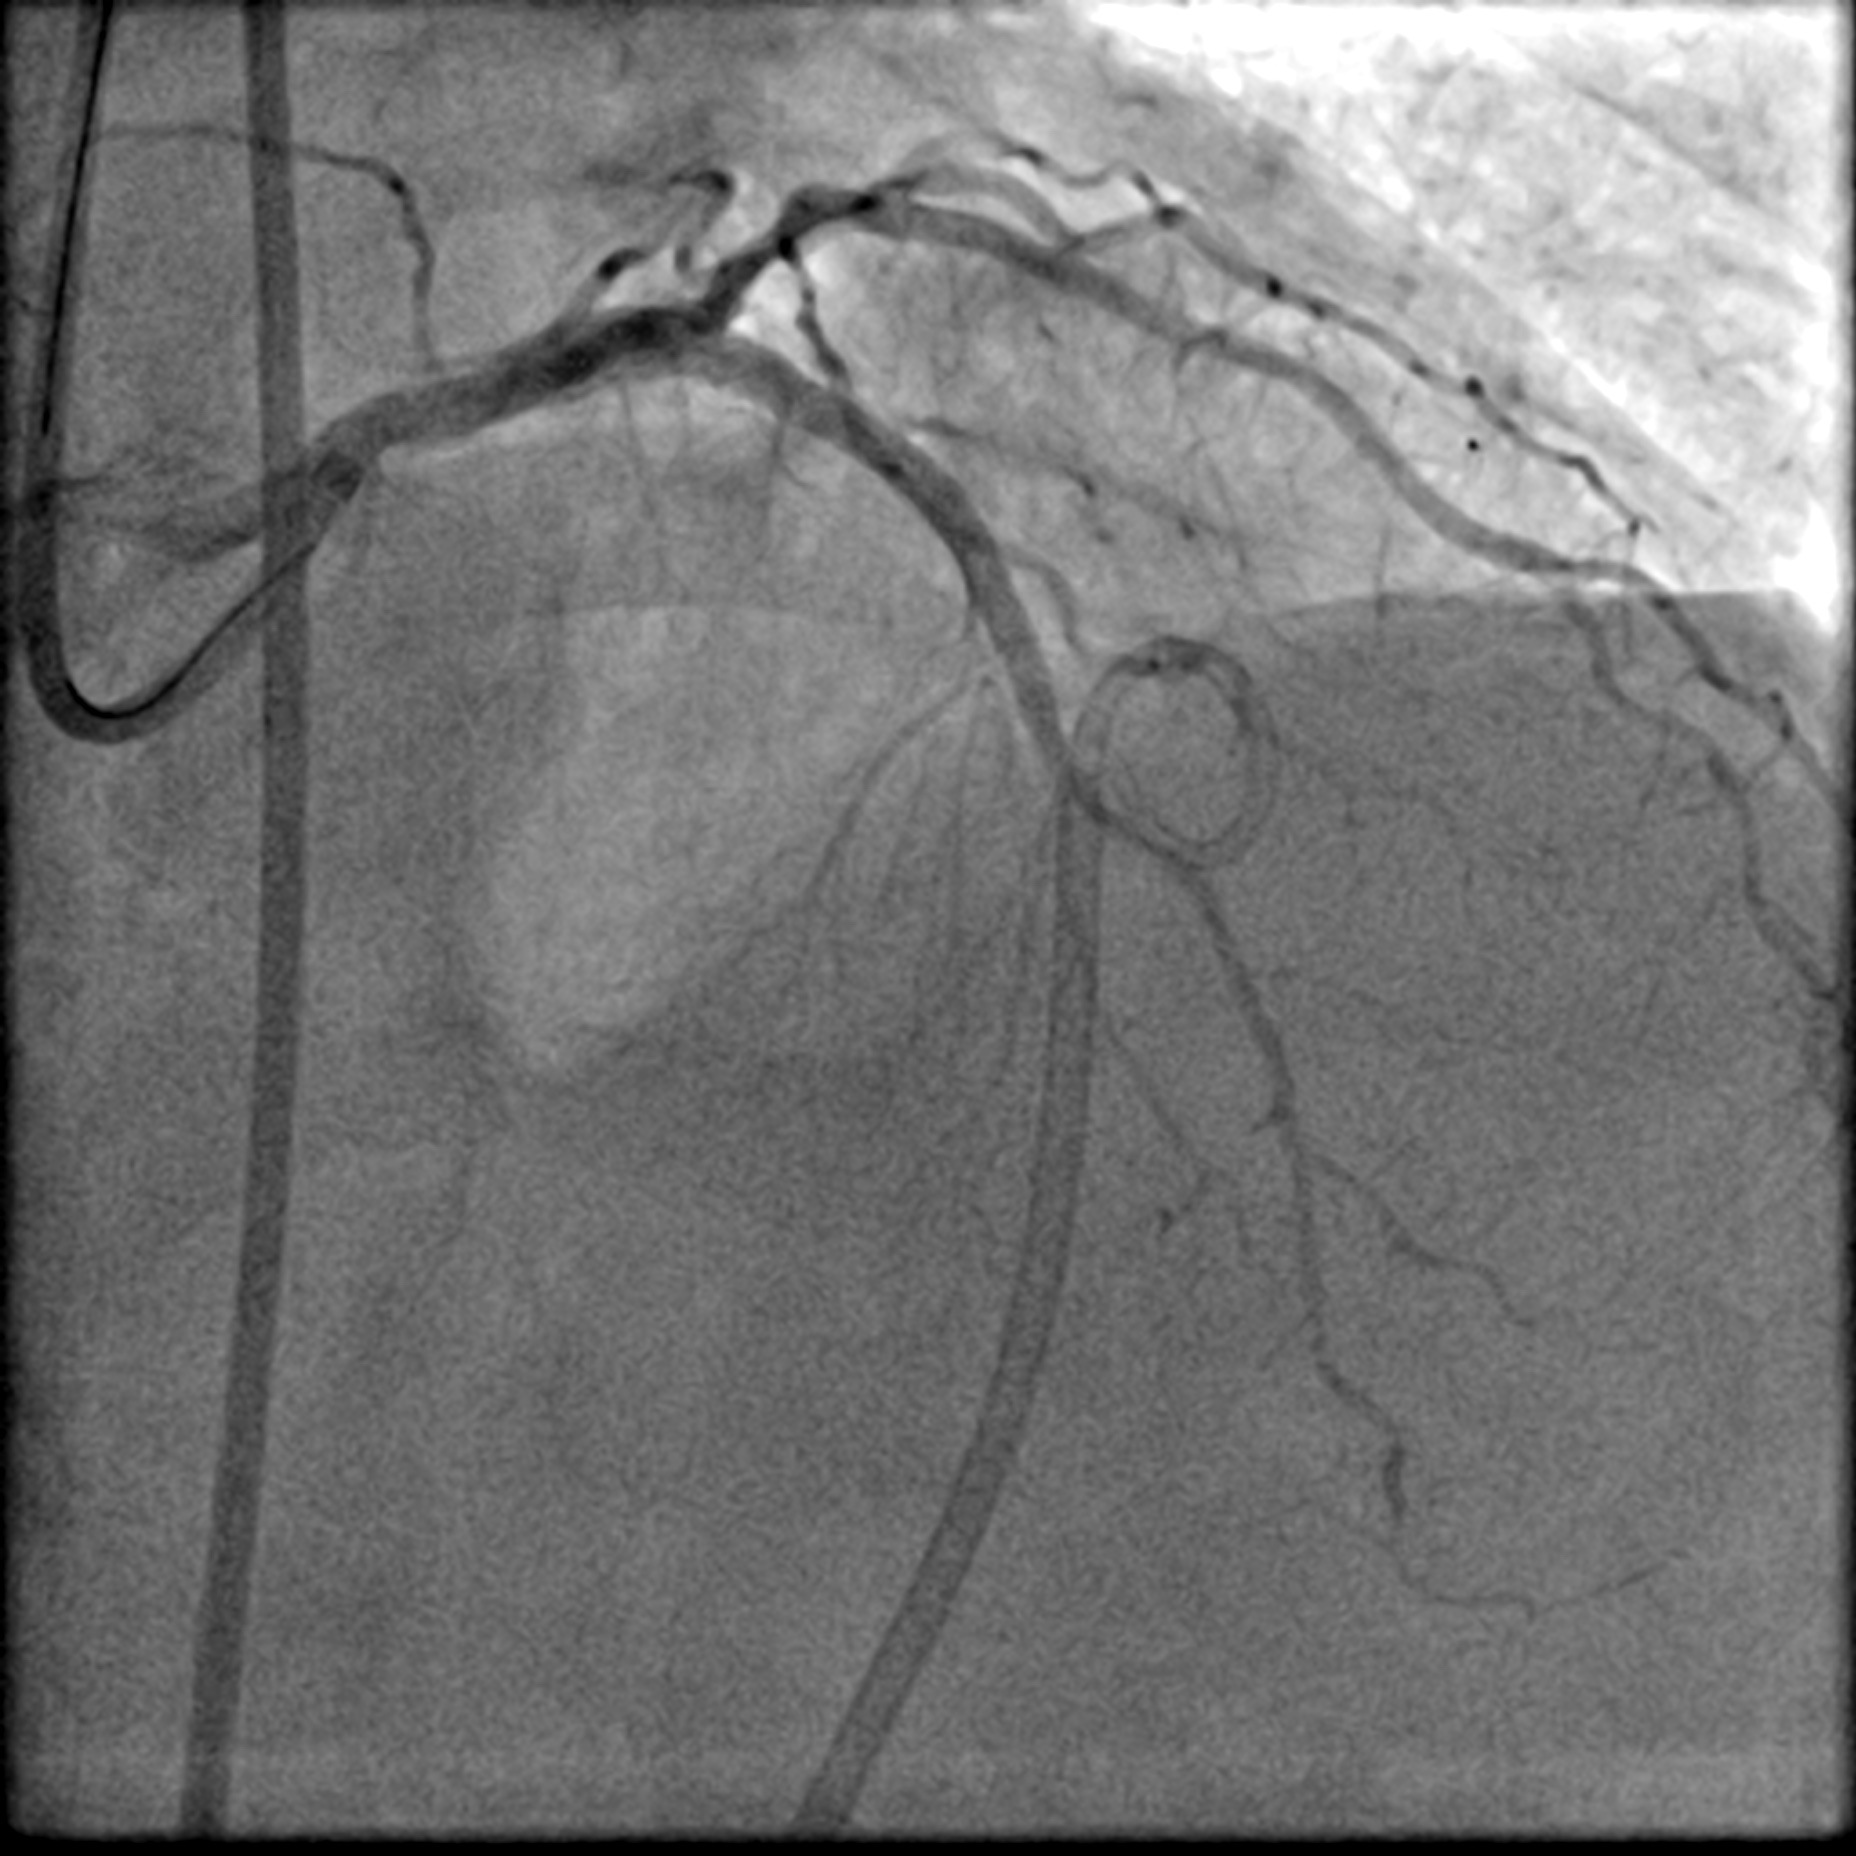

After positioning the ViperWire in the distal LAD, the OAS was delivered, and calcium debulking at low speed was performed safely. Afterward, the LAD was pre-dilated with a 2.5 mm scoring balloon and a 3.5 mm cutting balloon, while the LCx was pre-dilated with a 3.0 mm cutting balloon. A repeat angiogram revealed an Ellis 3 perforation in the proximal LAD, accompanied by a drop in the patient's blood pressure. Expeditiously, a 3.0 mm balloon was inflated at the perforation site, and its location was confirmed with an angiogram, which indicated immediate reduction of the perforation. A pigtail catheter was inserted simultaneously under echocardiographic guidance, and autologous blood transfusion was initiated. The perforation was covered with a 2.5 mm x 20 mm covered stent and post-dilated with a 3.0 mm NC balloon. This reduced the leak, but significant flow persisted. IVUS showed a gap between the stent strut and vessel wall near the LAD carina, allowing for persistent leakage. The covered stent was further post-dilated with a 3.5 mm NC balloon and a hugging balloon technique using two 2.5 mm balloons. These measures failed, as the maximal expansion of the 2.5 mm covered stent is limited to 3.0 mm. A Kissing Balloon Technique (KBT) was attempted at the bifurcation, but it proved futile. Finally, a second 3.5 mm covered stent was placed proximally, which successfully sealed the perforation, leaving only a trivial leak. The hemoperricardium resolved after 24 hours.

Case Summary